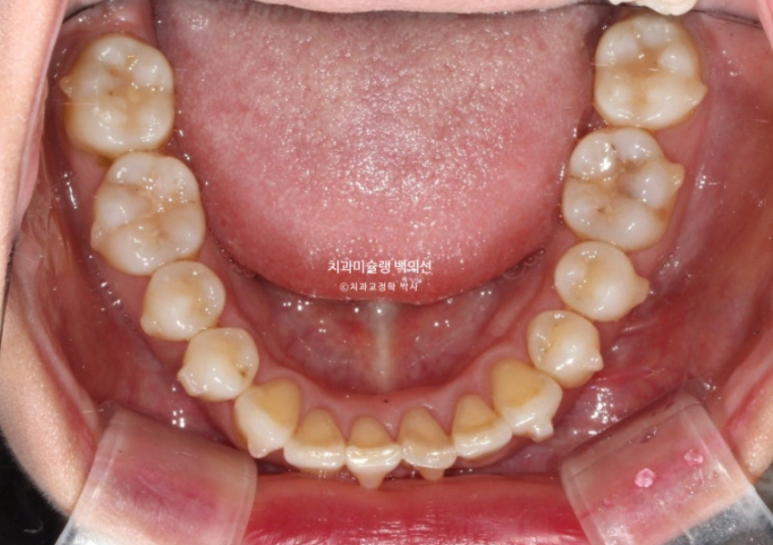

중심선이 맞아지고 과개교합도 해결되었고 아래앞니 치축 기울어짐이 보입니다.

덧니가 배열되며 반대교합도 해소가 되었습니다.

아래 앞니 배열이 약간 아쉽습니다.

이 부분들을 고치기 위해서 재제작에 들어갔습니다.

25년 5월부터 8월까지, 4달간 16개 추가장치를 모두 낀 후 치료를 마무리 했습니다.